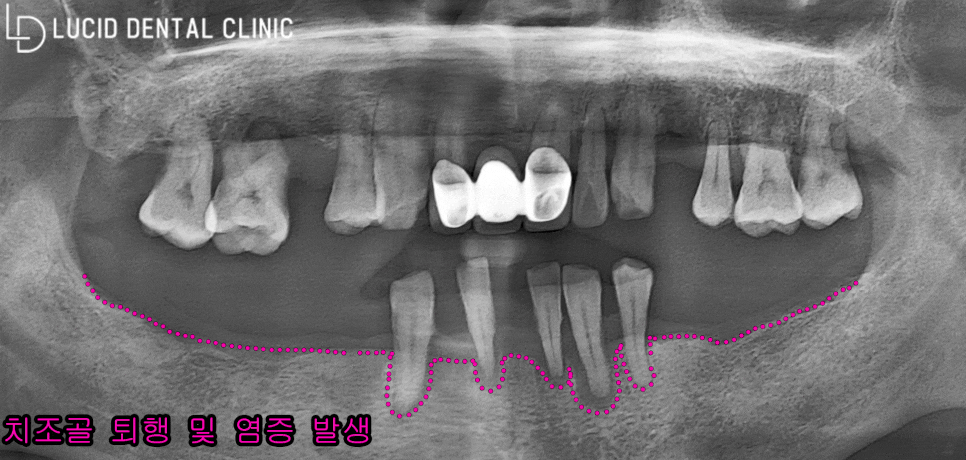

아래 보이는 파노라마 엑스레이를 통해

환자의 전체 구강 환경을 살펴봤습니다.

그 결과, 다수의 어금니 치아를 소실하며

몇 가지 문제점이 나타난 걸 알 수 있었는데요

간단하게 설명해 드리자면,

- 치조골 흡수

- 치근단 염증

(뿌리 주변 염증)

- 치아 정출

세 가지 문제가 나타나고 있었습니다.